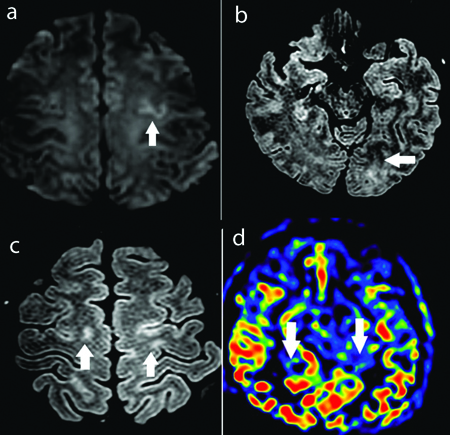

A 45-year-old female patient with no prior comorbidities was admitted with three-day history of high-grade intermittent fever followed by generalised tiredness. There was no history of joint pains, prior headache or seizures. Serology for dengue was positive and she was admitted in the Department of Internal Medicine. She was managed conservatively with hydration and antipyretics. She had drop in platelet counts to less than 10000/μL which required administration of platelet transfusion. Immediately after platelet transfusion, patient developed sudden onset of severe thunderclap headache associated with elevated blood pressures (>160/90 mm). The headache was noted to increase with blood pressure rise. There was no history of weakness of limbs or blurred vision. Clinical examination revealed no focal neurological deficits or meningeal signs. Magnetic Resonance Imaging (MRI) of the brain [Table/Fig-1] showed T2 weighted hyperintensities involving the left occipital and bilateral fronto parietal regions. There was evidence of focal restricted diffusion on Diffusion Weighted Imaging (DWI) sequences and no evidence of contrast enhancement. MR Angio (MRA) [Table/Fig-2] showed evidence of multifocal stenosis and narrowing involving the left vertebral and right posterior cerebral arteries. The scans were discussed with the neuroradiology team and were felt to be suggestive of Posterior Reversible Encephalopathy Syndrome (PRES). The differentials considered were primary CNS angiitis and cerebral venous thrombosis. She was managed with antioedema measures and anti-hypertensive agents-Mannitol at a dose of 0.5 mg/kg/day, hypertonic saline infusion at 15 mL per hour and labetalol 200 mg per day and had complete resolution of symptoms. She was discharged after improvement. At two weeks follow-up, patient was asymptomatic and had no deficits. Repeat MRI done after three months showed complete resolution of the abnormalities seen on the initial scans confirming a diagnosis of PRES [Table/Fig-3].

a) Axial DWI images showing focal cortical diffusion restriction in left frontal region (arrows). b,c) Axial FLAIR images showing cortical sub cortical high signal intensity in left occipital region and bilateral fronto parietal parasagittal location (arrows). d) Axial ASL colour map showing patchy region of elevated perfusion in bilateral occipital lobe (arrows).